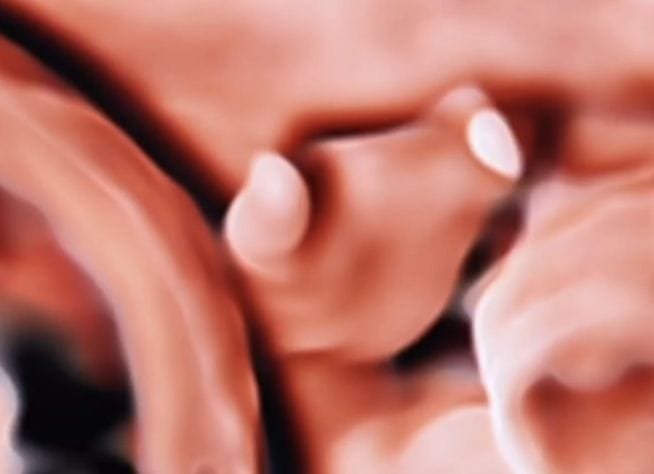

Symbrachydactyly is a rare congenital hand anomaly characterized by short, webbed, or missing fingers, often detectable on fetal ultrasound between 18–22 weeks gestation. Ultrasound may show missing digital phalanges or a “nubbin” appearance. While sometimes difficult to visualize due to hand movement, specialized scans can identify these skeletal deficiencies prenatally.

- Appearance: The hand may show short fingers (brachydactyly) or, in more severe cases, soft tissue nubs or complete absence of digits.